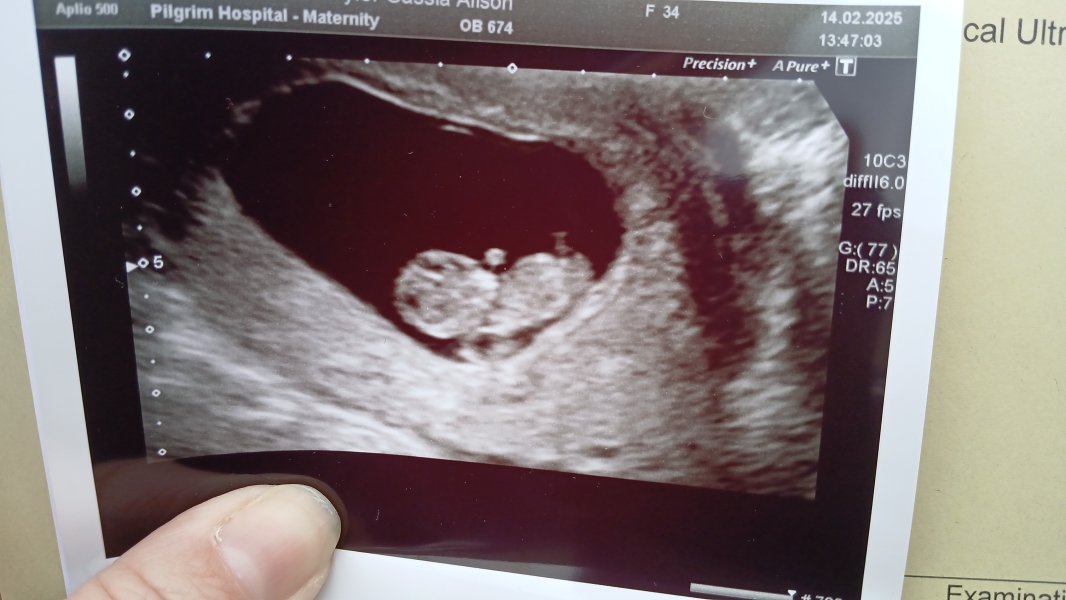

I have to admit that I have no idea what I'm looking for with regards to nub theory so unsure if anything is visable at 10 weeks.

Had an early scan due to bleeding but luckily everything with baby is fine.

Don't mind what sex baby is (DC3 third and final) but just curious to hear any guesses, based on nub theory or anything else.

It would help if I added the picture...

The nub theory unfortunately isn’t accurate until around 12+5. I am glad everything is okay.

I had an early scan with DD2 but I was only 7 weeks then and she looked like a t-rex, this scan actually looks like a baby so I just wondered if you could tell.

It super hard to see in this picture but my guess is a boy congratulations 😁